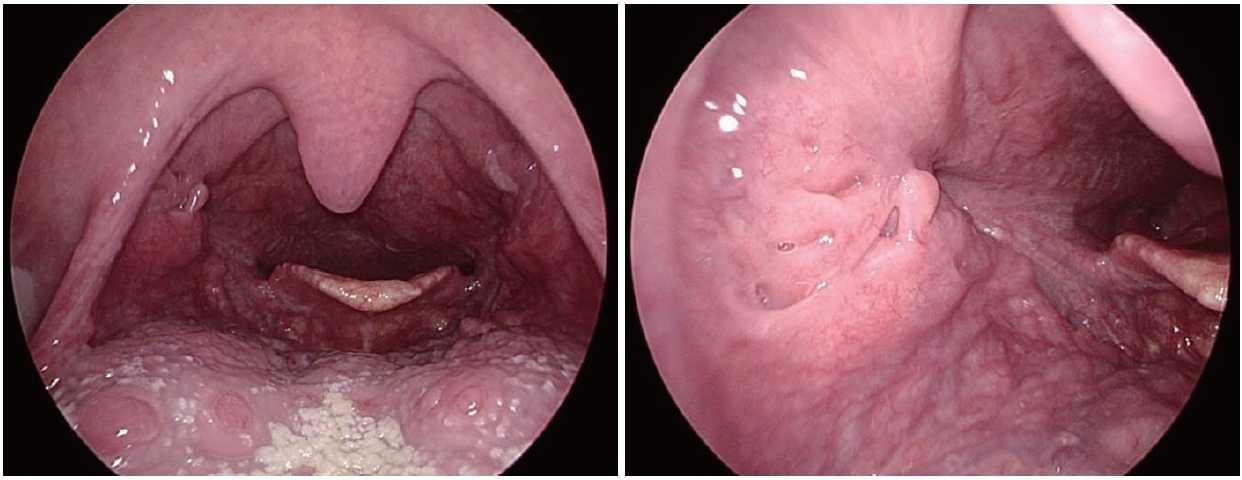

497 Malignant Peripheral Nerve Sheath Tumor Presenting as a Chronic Parotid Gland Mass: A Case Report

Wilson C. Zuñiga, Ida Marie Tabangay-Lim, Czarina Angelli L. Anastacio

Korean J Otorhinolaryngol-Head Neck Surg. 2025;68(11):497-502.   Published online September 3, 2025

DOI: https://doi.org/10.3342/kjorl-hns.2024.00535

kjorl-hns-2024-00535f1.jpgkjorl-hns-2024-00535f2.jpgkjorl-hns-2024-00535f3.jpgkjorl-hns-2024-00535f4.jpgkjorl-hns-2024-00535f5.jpg